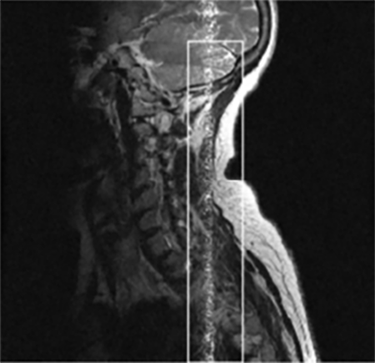

| Bulk Susceptibility (C-spine Fat Sat Uniformity) Poor chemical fat sat uniformity | ![]() | Poor B0 uniformity |